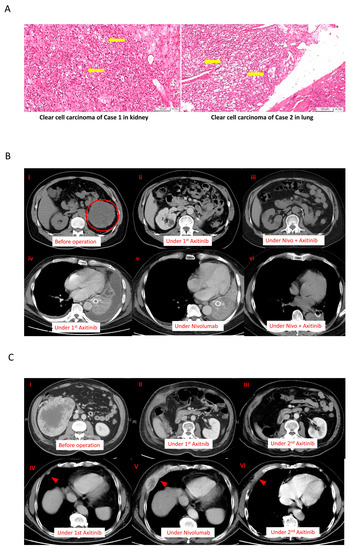

2. Case Description